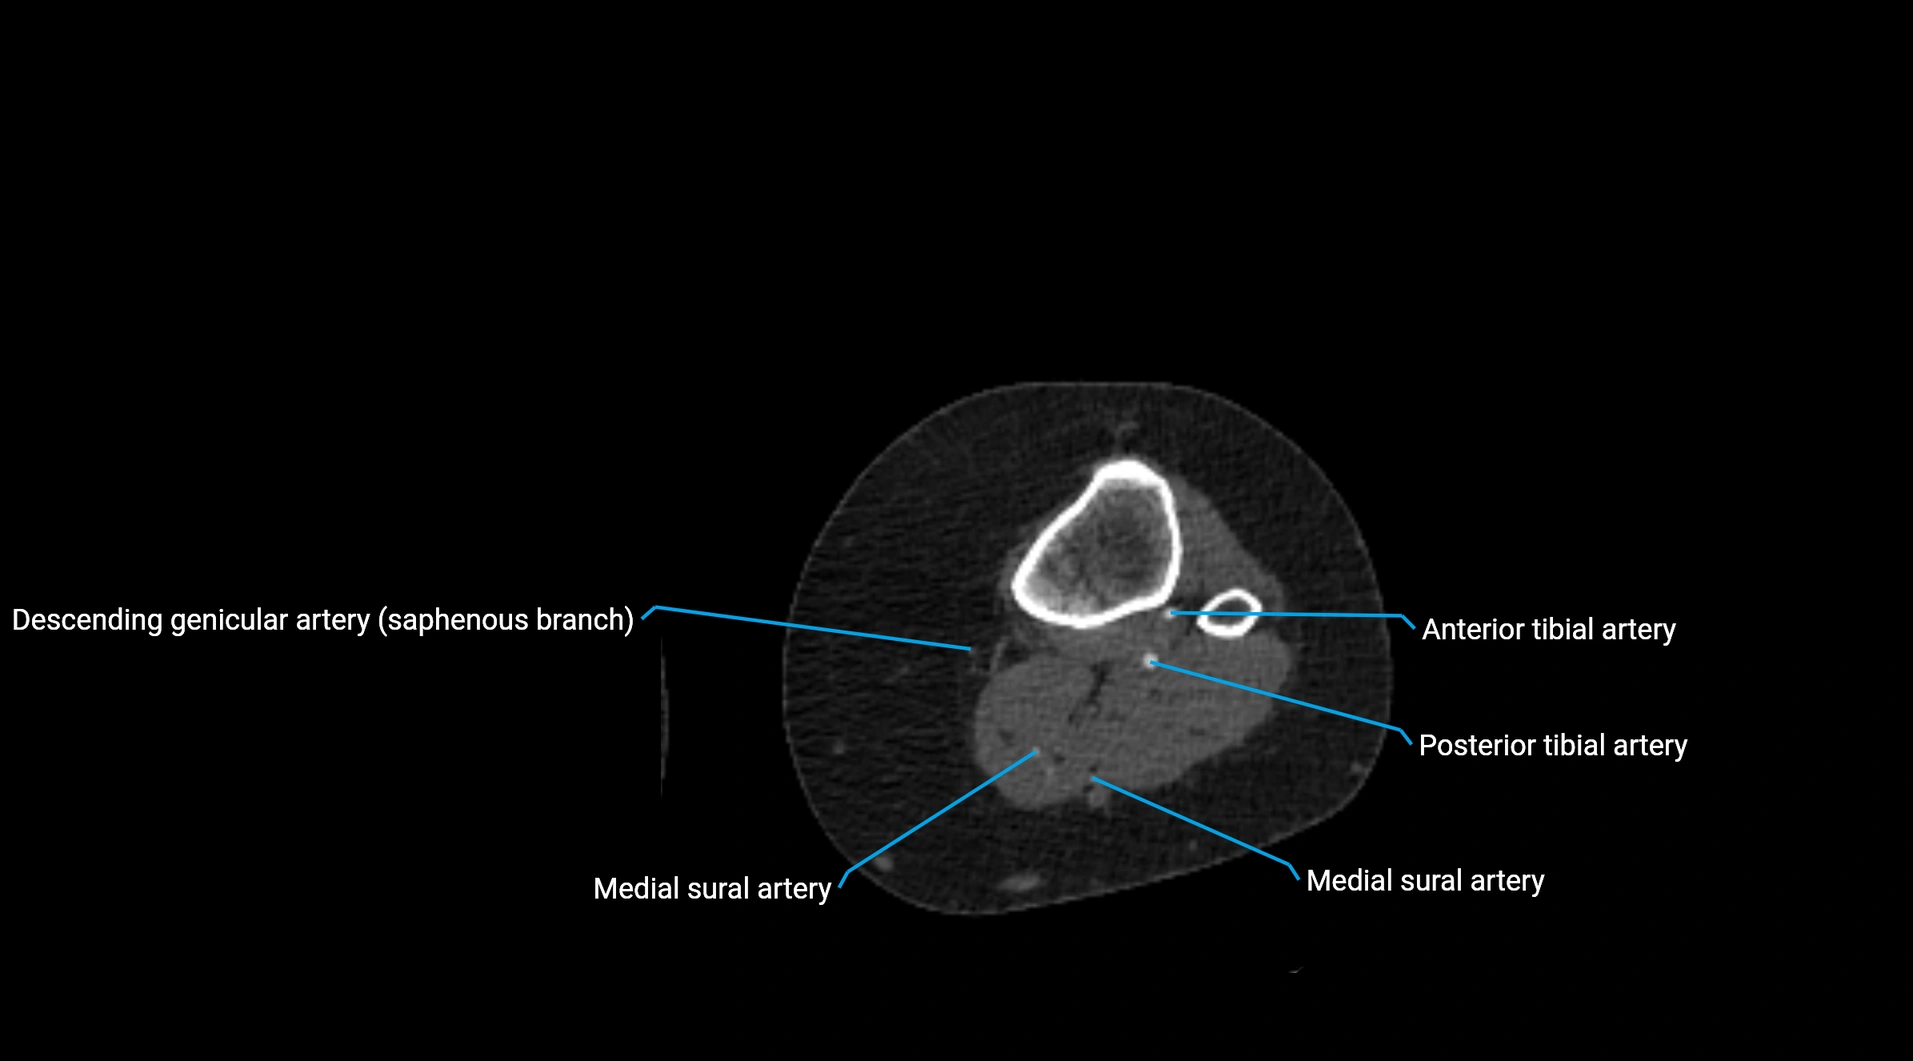

CT images

image